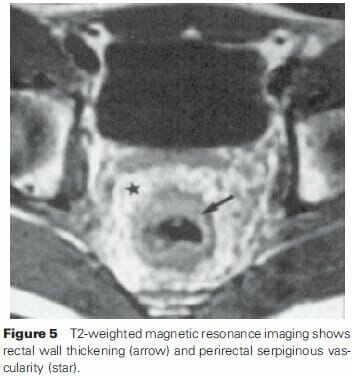

MRI

MRI can also enhance the diagnosis, especially in situations of rectal malformations8. In addition to the thickening seen, a high T2 signal intensity can be seen, thought to be due to the slow flow. Increased signal intensity is also noted in the perirectal fat with serpiginous structures correlating to the small vessels supplying the hemangioma (Figure 5). These MR features are not found in other clinical entities, and thus a higher specificity, especially over CT can help in diagnosis. Though hemorrhoids can present with similar T2 findings, the difference in the two entities can be seen by location and lack of perirectal fat extension or abnormalities in hemorrhoids. Phleboliths and calcifications are less easily detected on MR vs. CT or plain film.